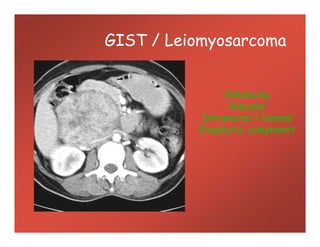

GIST / Leiomyosarcoma

Enhancing

Vascular

Intramural / luminal

Exophytic component